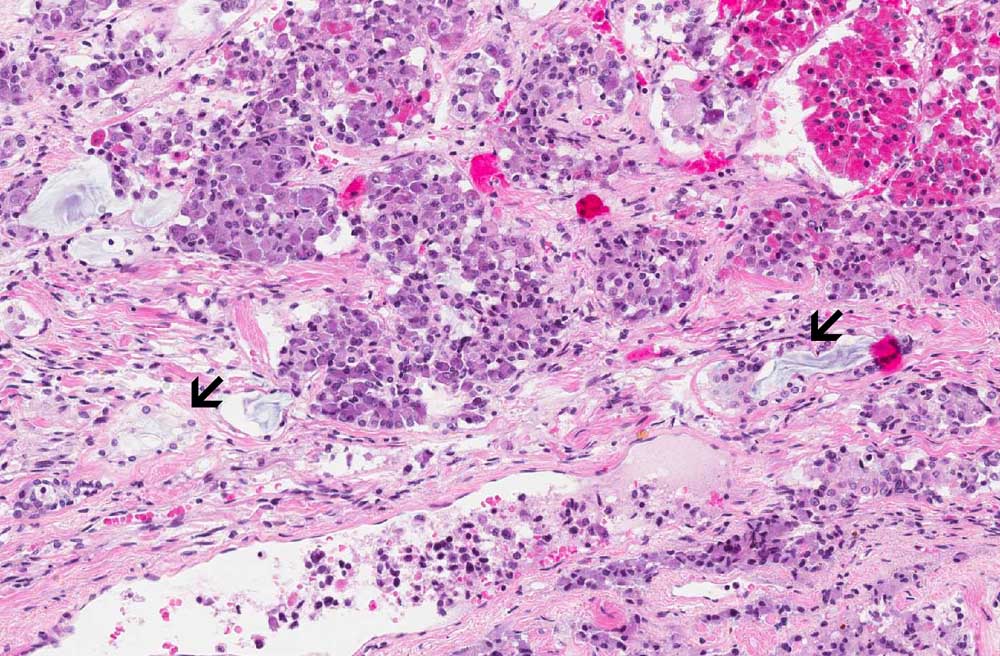

Area 1: Note that within the pale area are clusters of mucin producing glands with basally located nuclei associated with fibrosis.This location is not the most typical location of these glands. Fibrosis should not be associated with ectopic salivary glands.

• The image being shown here is largely composed of the anterior pituitary. Portion of the posterior pituitary is also present. The nests of epithelial glands in the anterior are rather monotonous in size and there is no evidence of hyperplasia or adenoma formation. Second, they are associated with a substantial amount of fibrosis. This raises a possibility of metastatic adenocarcinoma but no cancer is found on autopsy.

• There is a triangular pale area with mucin producing glands. These glands are most consistent suggestive of ectopic salivary glands. However, there is fibrosis associated with these glands and the glands also look atypical.

• The true idendity of these glands are difficult to be elucidated. Although they may represent ectopic salvary glands in the pituitary, the location is unusual as they tend to be found at the interface between anterior and posterior pituitary.

• Ectopic salivary glands should not be mistaken as metastatic carcinoma. These glands are typically found on the surface of the pituitary or in the neurohypophysis, often at the interface between the neurohypophysis (posterior pituitary) and adenohypophysis (anterior pituitary) just posterior to the pars intermedia. They are composed of single layer of columnar or cuboidal epithelium with finely granular cytoplasm that is PAS positive. Oncocytic changes is also often. Mucin producing cells can also be present as illustrated in this case. What is unusual in this case is that there is also fibrosis around these glands.